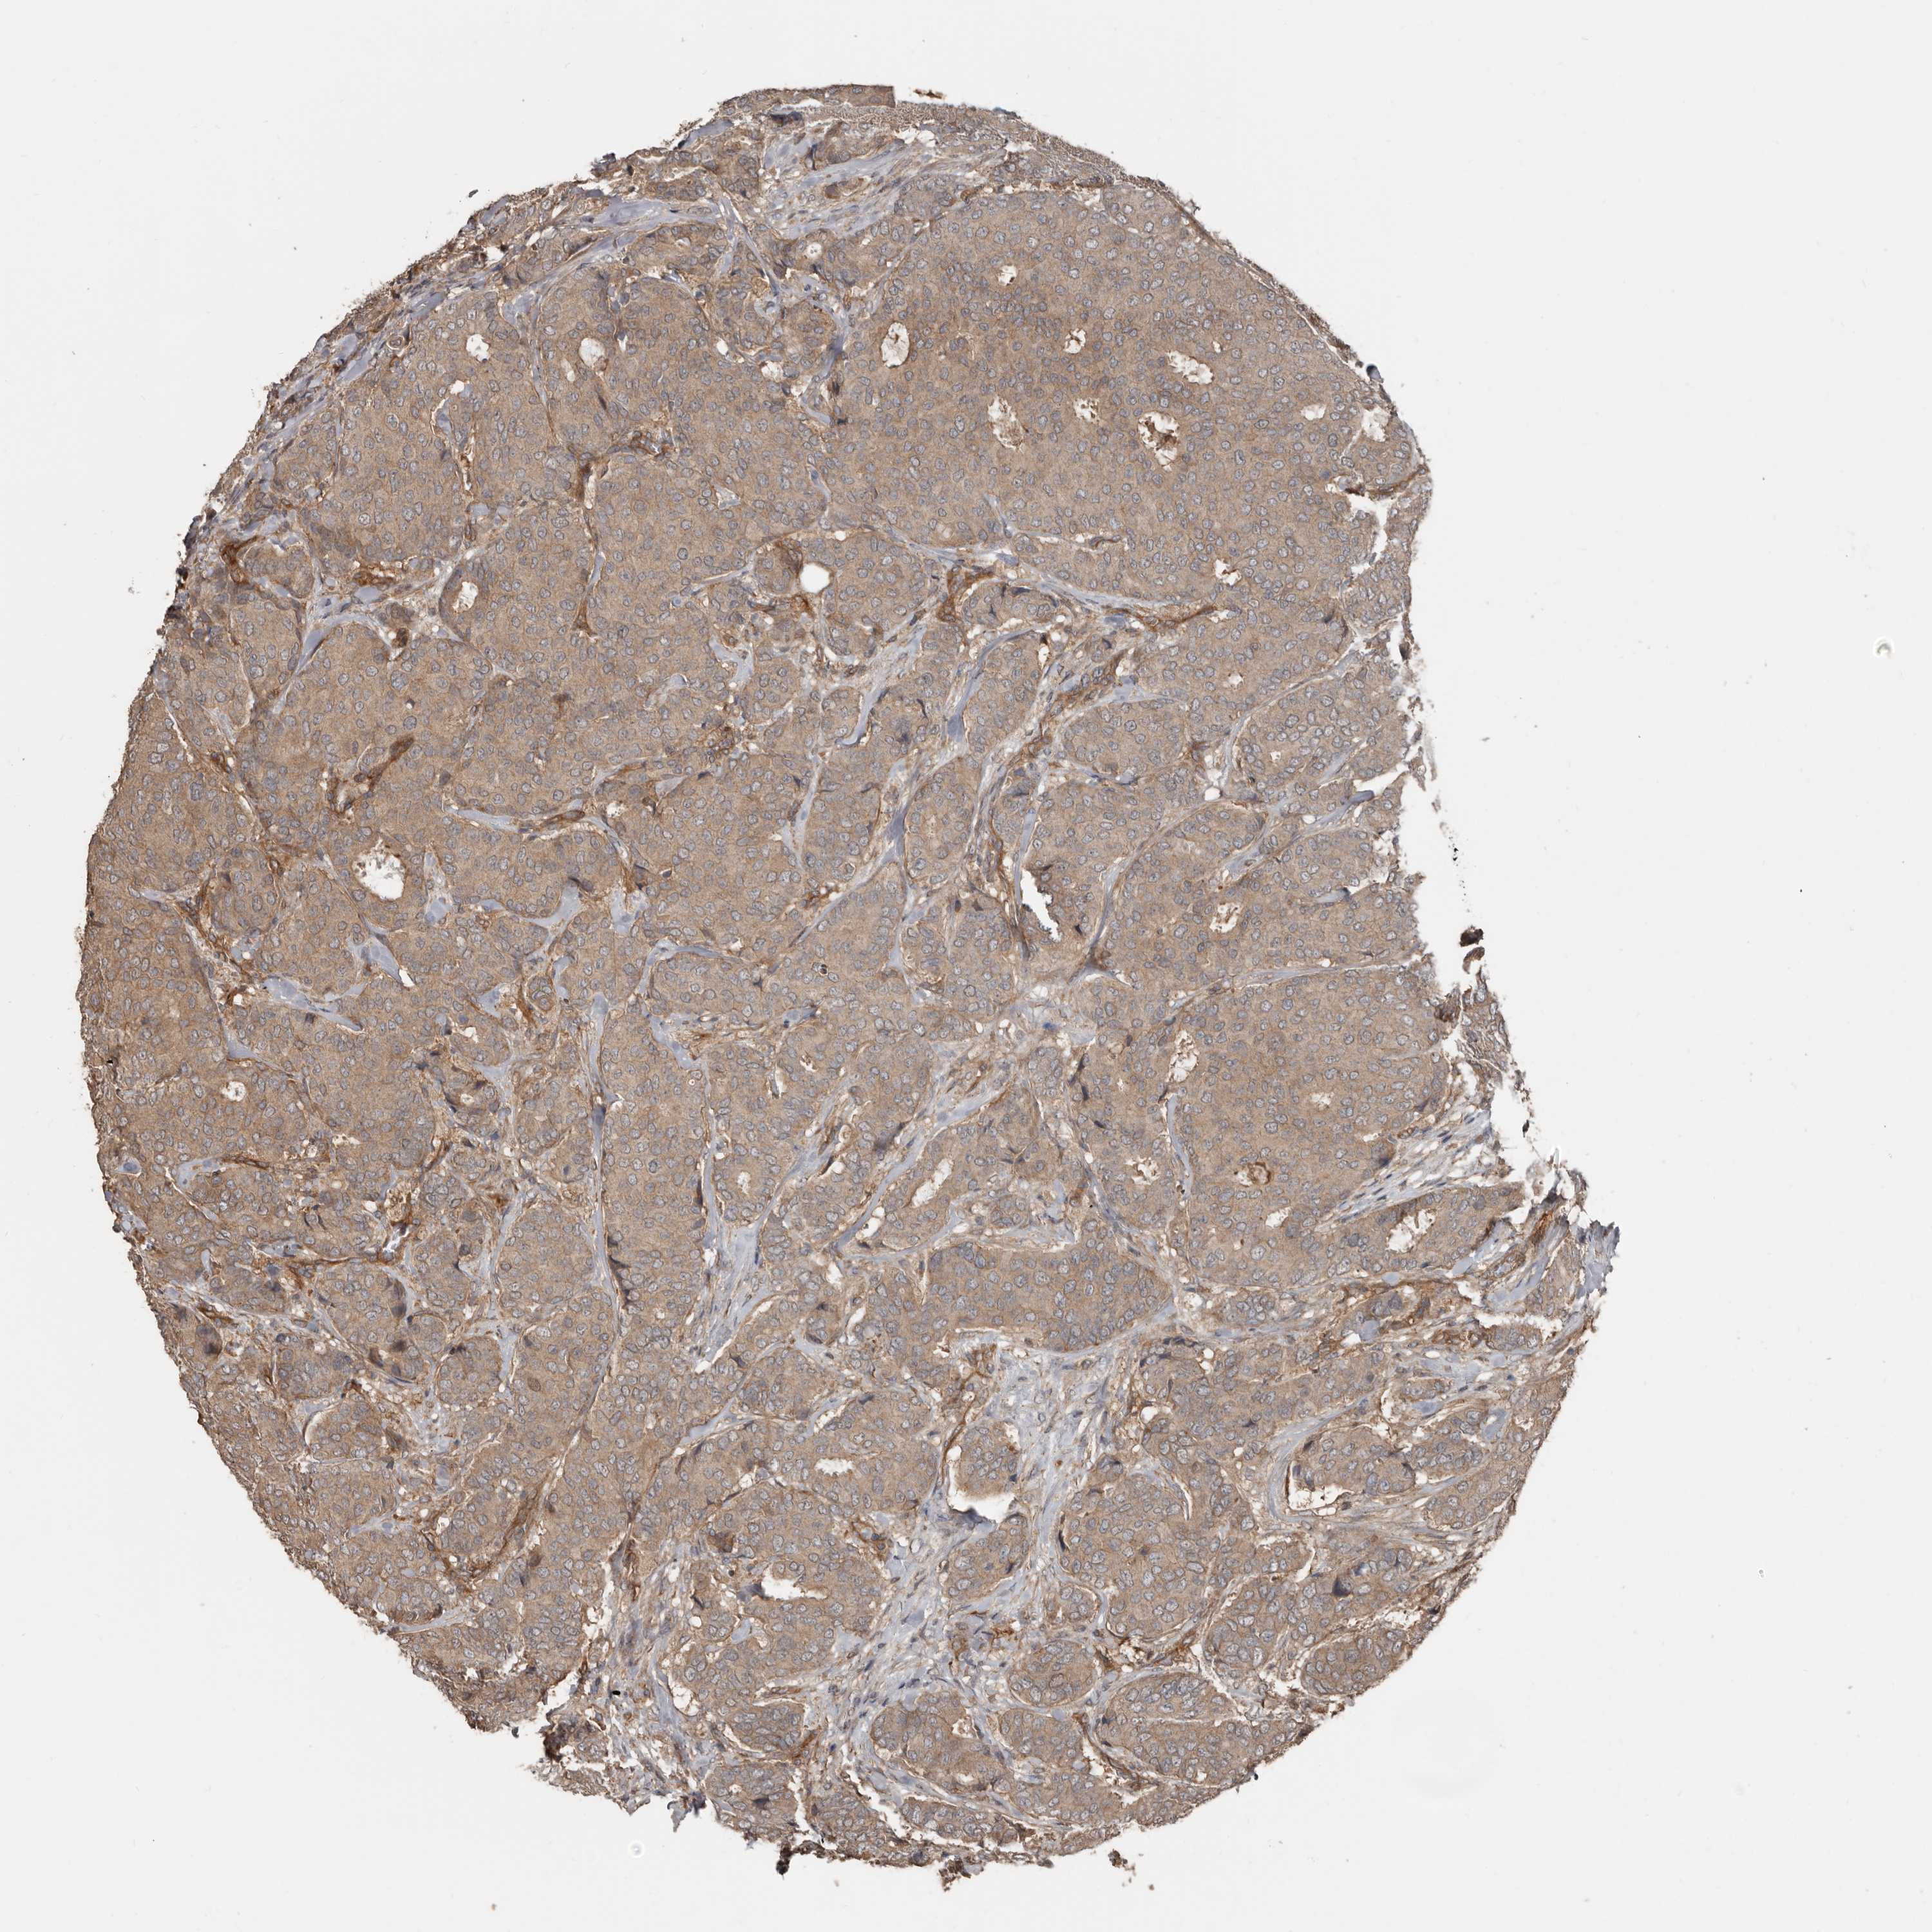

CANCER BREAST CANCER Show tissue menu

BRCA TCGA BRCA VALIDATION PROTEIN EXPRESSION